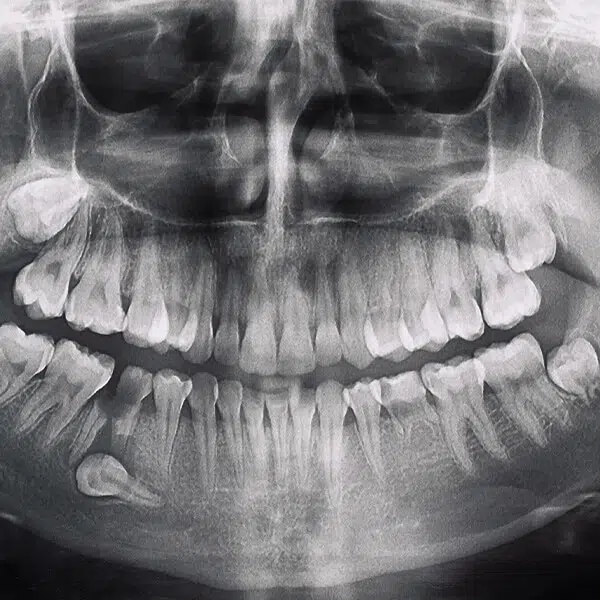

Pierwszym krokiem w leczeniu zatrzymanych zębów jest szczegółowa konsultacja stomatologiczna i diagnostyka. Wykonujemy panoramiczne zdjęcia rentgenowskie oraz stożkową tomografię komputerową, aby dokładnie ocenić położenie zatrzymanego zęba oraz jego wpływ na otaczające tkanki i struktury zębowe.

Zanim przystąpimy do zabiegu, pacjent przechodzi szczegółową konsultację stomatologiczną, która obejmuje badanie jamy ustnej oraz diagnostykę obrazową (pantomogram, tomografia komputerowa). Na tej podstawie opracowujemy indywidualny plan leczenia.

Pierwszym krokiem w przygotowaniu do leczenia protetycznego jest szczegółowa konsultacja stomatologiczna. Podczas tej wizyty przeprowadzamy wywiad medyczny, aby zrozumieć historię zdrowia pacjenta oraz jego oczekiwania i potrzeby. Następnie wykonujemy szereg badań diagnostycznych, w tym zdjęcia rentgenowskie (Pantomogram, RVG) oraz tomografię komputerową, aby dokładnie ocenić stan jamy ustnej, kości i tkanek miękkich.

- Przed przystąpieniem do zabiegu wykonujemy szczegółowe badania diagnostyczne, w tym zdjęcia rentgenowskie i tomografię komputerową, aby dokładnie ocenić stan korzenia zęba i otaczających tkanek.